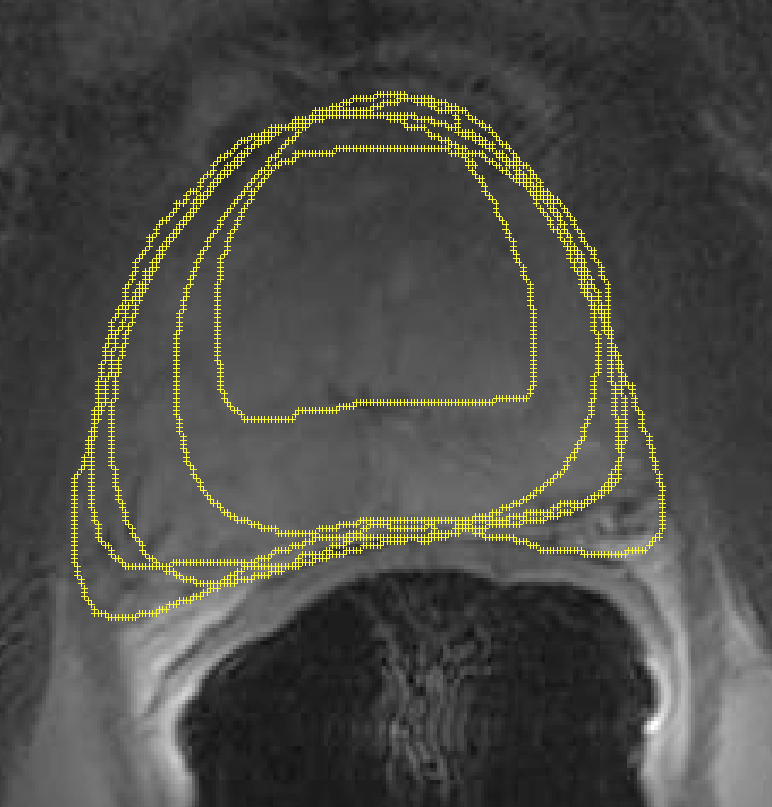

We generated 500 images from their corresponding gold-standard images. Furthermore, we generated 20 different segments for each image, assuming that there were 20 users. Figure 4 shows three examples of real and synthetic TRUS images. One should bear in mind that the purpose here was not to simulate the images realistically, but rather to have a base from which to generate variable segments from a perfect segment. Figure 5 shows an example of the gold segments and simulated user contours. The variability, coupled with the gold segment, is what is needed to validate our approach.

Refer to caption

Figure 5: Sample image shows gold segments and consensus contours (left). The users have drawn the contour differently (middle, with the gold contour superimposed). The inverted region (middle) is magnified (right) to emphasize details of the variability.